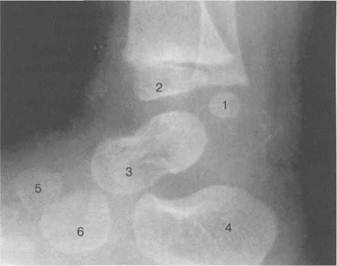

Рис. 19.136. Рентгенограмма голеностопного сустава (1 год).

1 — таранная кость; 2 — пяточная кость; 3 — больше-берцовая кость; 4 — малоберцовая кость.